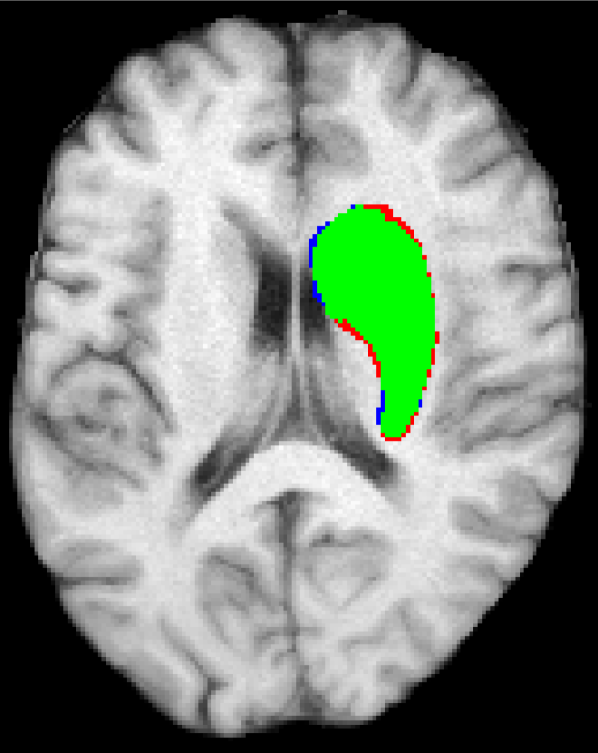

Representative examples of the qualitative results from the proposed method can be found in Figure 4. Cases 9 and 15 represent the overall results of the proposed methodology, correctly detecting the lesions in most cases with an outline that approximates the provided gold standard. Among the observed limitations are inaccurate borders and over/under segmentation of certain regions. For instance, in case 5 the lesion was undersegmented due to a heterogeneous appearance of the gold standard lesion while in case 13 two false positive lesions are detected due to the previous existence of chronic stroke lesions with a similar appearance.

Figure 4: Output segmentation masks of representative cases from the training images of ISLES 2015 SISS dataset. On all images, true positives are denoted in green, false positives in red and false negatives in blue.